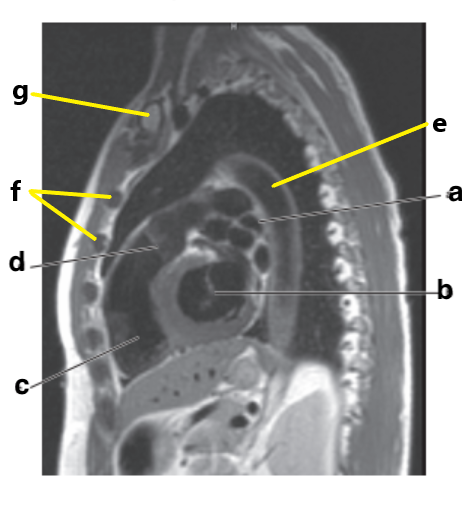

What is letter b ?

Esophagus

Which letter is the Pulmonary trunk ?

d

Which letter is the Descending aorta ?

f

Left atrium

What is letter f ?

Diaphragm

What is letter e ?

Vertebral body

Aortic Arch

Which letter is the descending thoracic aorta ?

e

What is letter g ?

Descending thoracic aorta

Descending aorta

What is letter c ?

Trachea

Thoracic vertebra

Sternum